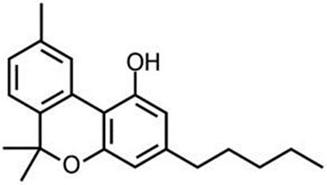

Physical and Chemical Properties of Active Pharmaceutical Ingredient CBN

CBN is a stable, highly lipophilic cannabinoid compound. It is insoluble in water, but soluble in organic solvents.

| International Non-proprietary Name: | Cannabinol (abbreviated CBN) | |

| International Union of Pure and Applied Chemistry Name: | 6,6,9-trimethyl-3-pentyl-benzo[c]chromen-1-ol | |

| Chemical Abstracts Service Registration Number: | 521-35-7 | |

| United States Adopted Name: | Cannabinol |

The molecular formula is C21H26O2 and the molecular weight is 310.43 g/mol. CBN has no chiral centers.

Figure 1 Structural Formula of CBN

CBN occurs naturally as a trace component of Cannabis, or as a degradation product of D9-THC. However, our product candidates utilizing CBN contain highly purified synthetic CBN, rather than a biological extract.